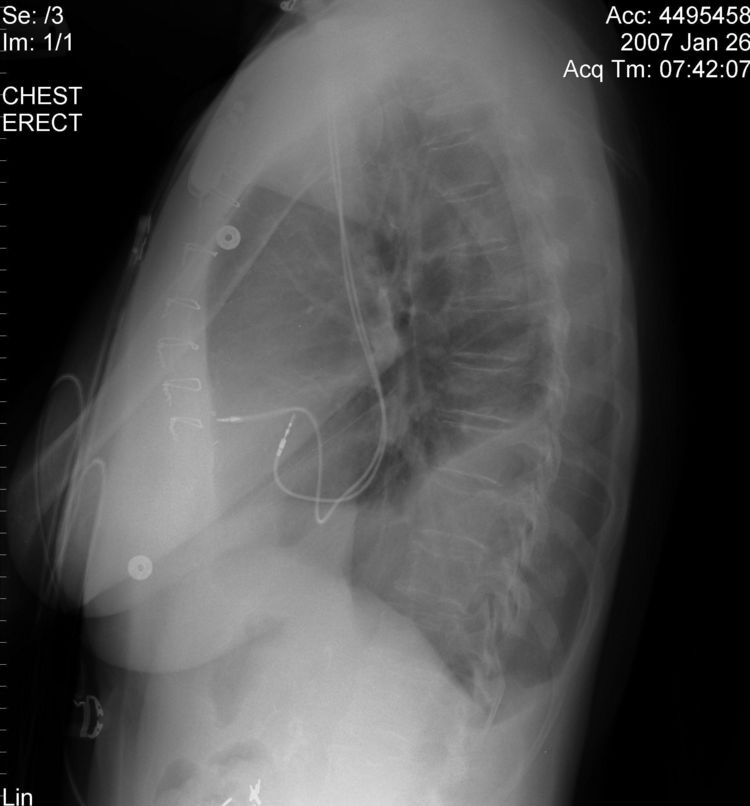

Persistent Left Superior Vena Cava

The above CXR show the atrial and ventricular pacemaker lead passing through a persistent left sided SVC.